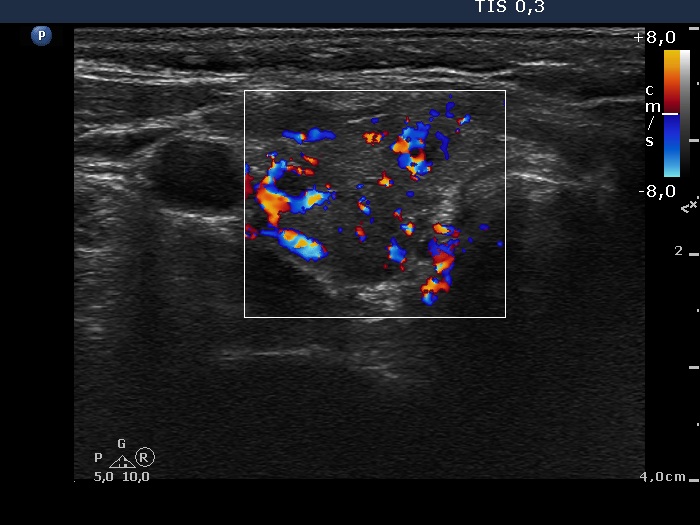

First examination (first row):

Clinical presentation: A 28-year-old woman was referred for evaluation of a recurrent hyperthyroidism. She underwent radioiodine therapy 3 years ago. She did not require replacement therapy and was euthyroid in the previous 30 months. Her original complaints recurred for two months, including 8 kg loss in weight and tachycardia.

Palpation: Both thyroids were enlarged and moderately firm.

Result of blood test: hyperthyroidism (TSH undetectable, FT4 38.6 pM/L).

Ultrasonography: A diffusely hypoechogenic thyroid was found with multiple more hypoechogenic lesions. None of them corresponded to a nodule. The vascularization was increased.Daily 20 mg methimazole was administered and repeat radioiodine therapy was advised after reaching the euthyroid state.